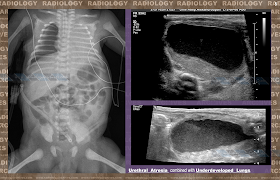

Rare & Unusual Pediatric Conditions are Always Present

S. Deftereos

,

A. Zazaliari

, E. Vranou,

P. Prassopoulos

Democritus University of Thrace

, Alexandroupolis, Greece